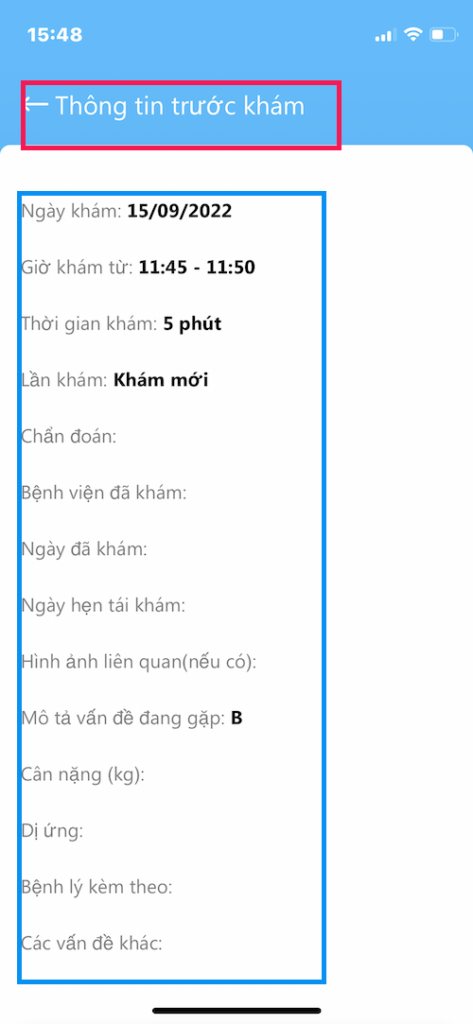

XEM CHI TIẾT

Thông tin trước khám

- Các thông tin do bệnh nhân cung cấp

- Các chi tiết khai báo lúc đặt lịch khám

- Lưu ý cung cấp giấy xuất viện, toa thuốc là quan trọng